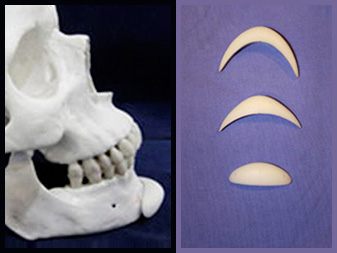

탑클래스성형외과에서는 개인별 이마의 모양과 크기가 다르기 때문에 1:1 맞춤형 이마석고 모형을 본 떠 보형물을

준비합니다. FDA 승인을 받은 보형물의 사용으로 안전하며, 이물감이 적고 염증 유발의 걱정이 적습니다.

Check 01

Check 01

수면, 부분마취 후 입안절개를 시행합니다.

Check 02

Check 02

골막을 거상하여 보형물이 위치할 공간을 확보합니다.

Check 03

Check 03

확보한 공간에 보형물을 삽입하고 고정시킵니다.

Check 04

Check 04

절개 부위를 봉합합니다.

입안 최소절개를 통해 다양한 크기, 모양의 보형물 중 개개인에 맞는 보형물을 사용합니다. 탑클래스 성형외과에서는

입안 최소절개를 통해 다양한 크기, 모양의 보형물 중 개개인에 맞는 보형물을 사용합니다. 탑클래스 성형외과에서는

Screw고정을 시행하여 근육의 움직임에 의한 보형물 이동을 예방하고 자연스럽고 어려 보이는 효과를 극대화시켜

줍니다.